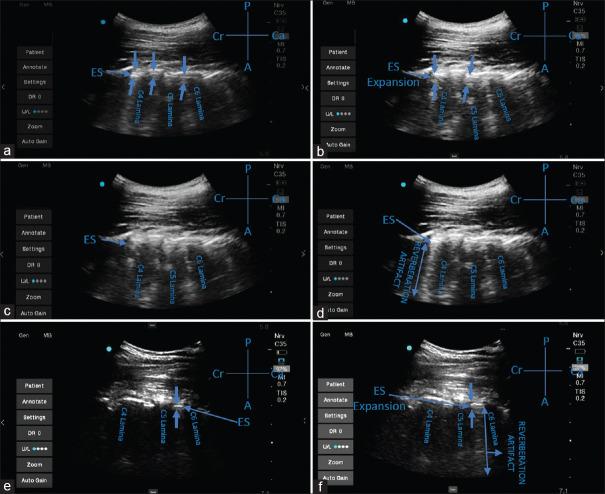

RESULTS

The pre-procedural UVS by the transverse interlaminar view (x/21) was 2.81 ± 1.94 and by the oblique paramedian sagittal view was 16.66 ± 2.39 with UVS being best in the paramedian oblique sagittal view (P- value < 0.05). The comparison of depth of the epidural space identified by USG and that by the LOR technique was statistically insignificant (P = 0.83). The average puncture attempts were 1.1 ± 0.3. Post-procedure US epidural catheter confirmation score (x/3) was 1.44 ± 0.44 with either epidural space expansion or microbubbles seen or both.

结果

横突间矢状视图(x/21)的术前 UVS 为 2.81±1.94,斜旁正中矢状视图为 16.66±2.39,旁正中斜矢状视图的 UVS 最佳(P<0.05)。USG 测量的硬膜外空间深度与 LOR 技术测量的深度无统计学差异(P=0.83)。平均穿刺尝试次数为 1.1±0.3。术后 US 硬膜外导管确认评分(x/3)为 1.44±0.44,可见硬膜外空间扩张或微泡或两者均可见。